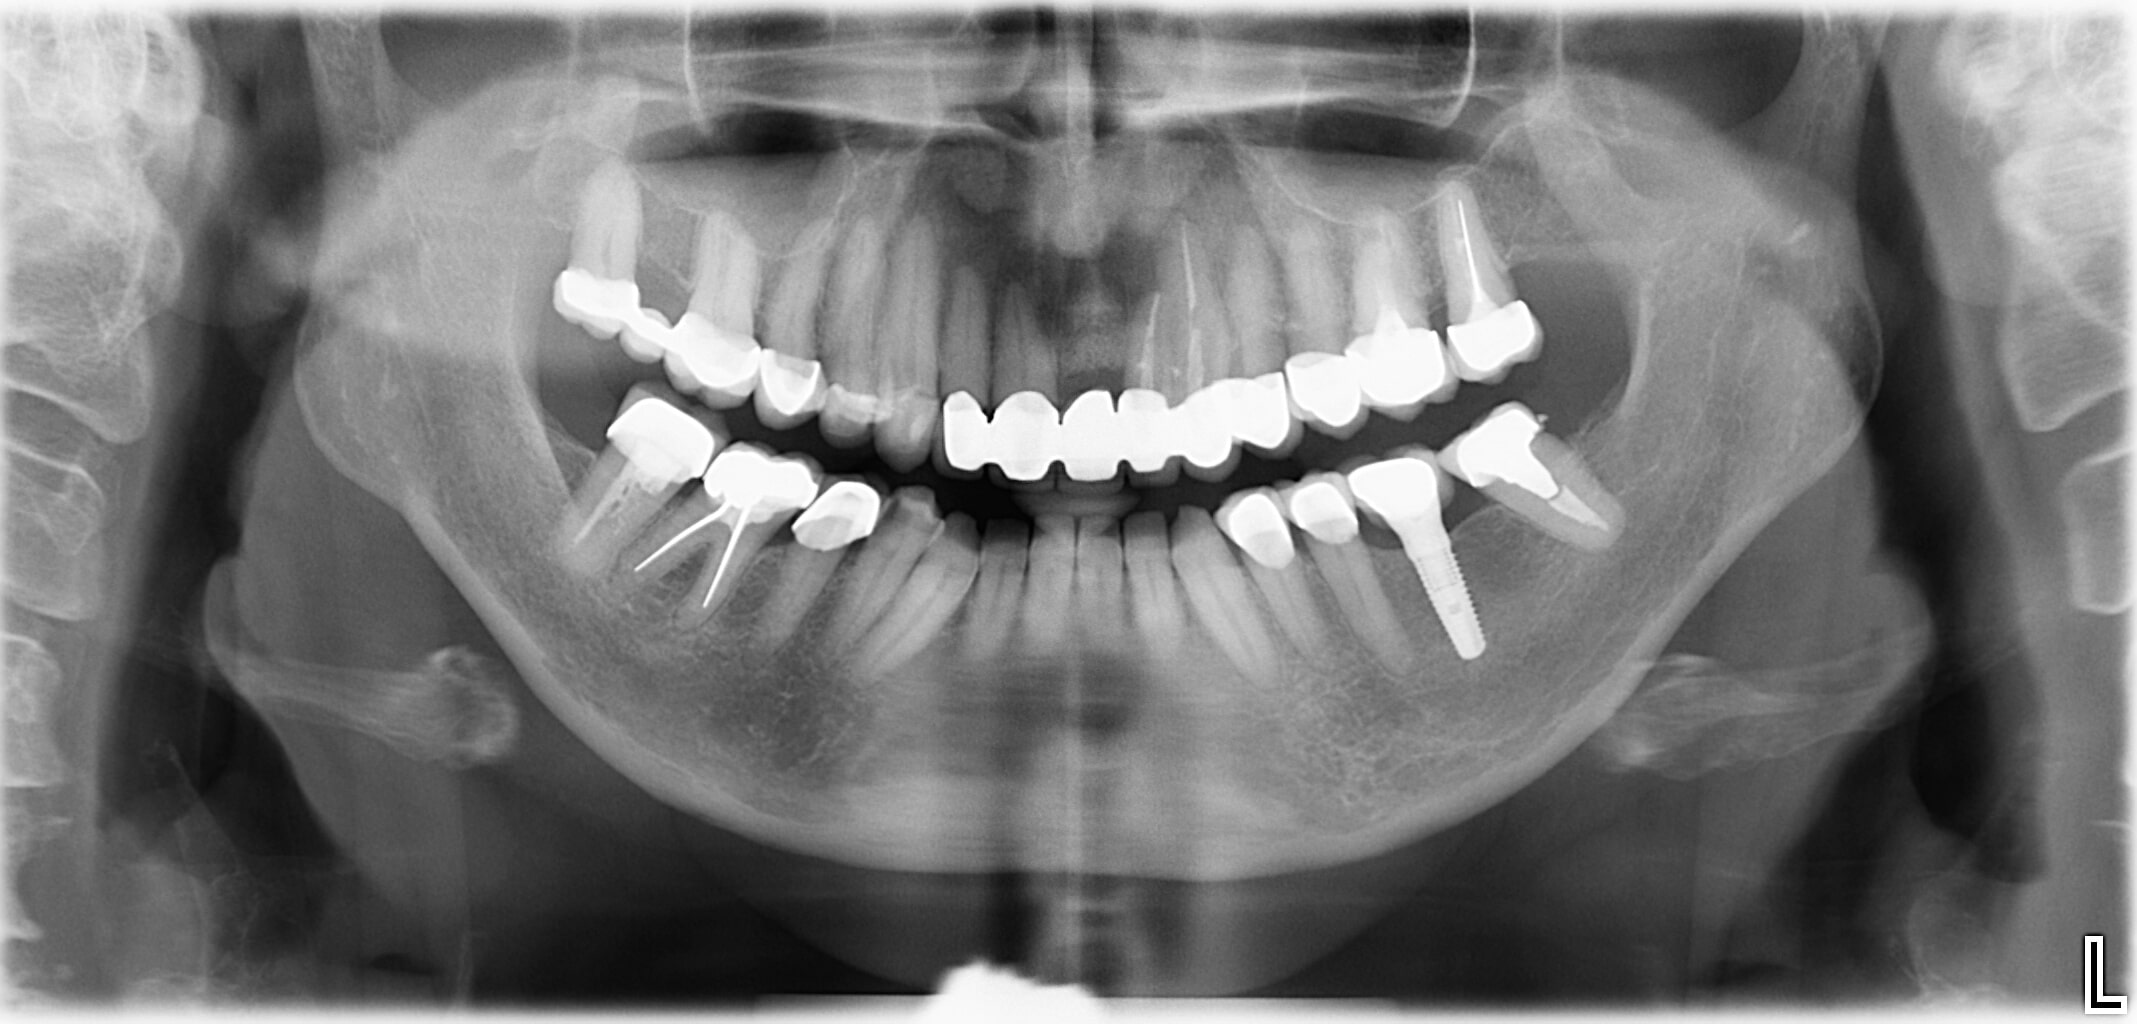

Wenn am Ende der Zahnreihe Zähne fehlen, muss eine herausnehmbare Prothese hergestellt werden. Für eine festsitzende Prothese wäre ein hinterer „Pfeiler“ zur Befestigung nötig. Durch den Einsatz von Implantaten kann man auf den herausnehmbaren Zahnersatz verzichten. Das bringt Vorteile beim Kauen und hilft bei der Vorbeugung funktioneller Gelenkerkrankungen.

- Am Ende der Zahnreihe fehlen ein oder mehrere Zähne

- Natürliche Zähne begrenzen den zahnlosen Abschnitt nur auf einer Seite

- Ein zahngetragener Zahnersatz (Brücke) ist nicht möglich

- Versorgung in der klassischen Zahnersatzkunde: Teilprothese abnehmbar

Die Lösung

- Eine rein implantatgetragene Verbundbrücke oder Einzelzahnimplantate vermeiden Brücken und abnehmbare Teilprothesen.

- Implantate als zusätzliche Pfeiler: Brücke auf natürlichen Zähnen und Implantaten